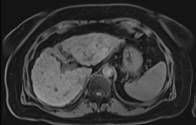

“Moving from about 15-20 seconds to 8 seconds is a major change in breath hold. It’s important for people who are very sick, like chronic liver disease patients, or for pediatric patients,” continued Taouli. “We’re also able to combine two sequences into one breath hold for patients able to do a longer breath hold. For example, we can do two arterial phase acquisitions in the liver with a single breath hold of about 16 seconds.”

The ability to reduce breath holds with Caipirinha can lead to better patient experiences and more efficient workflows for body MR imaging exams. “Our technologists appreciate that it’s quick,” said Taouli, “and patient acceptability is better.”